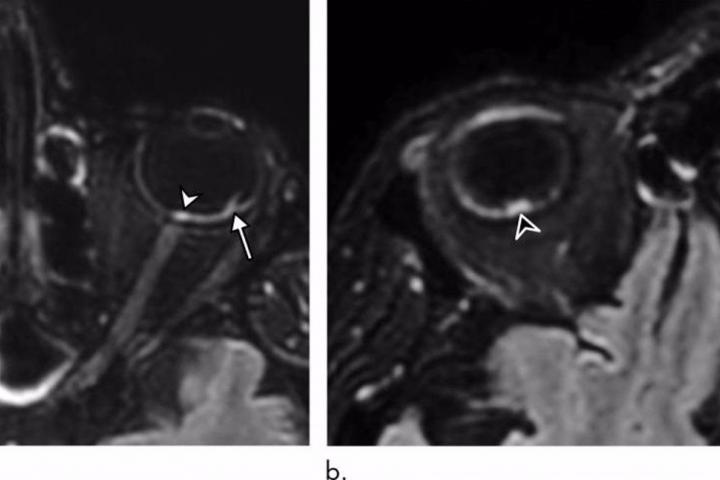

De los 129 pacientes, nueve (7%) tenían hallazgos anormales en la resonancia magnética del globo ocular. Las resonancias magnéticas mostraron uno o más nódulos en la parte posterior, o polo posterior, del globo ocular. Ocho de los nueve pacientes habían pasado un tiempo en la unidad de cuidados intensivos (UCI) por COVID-19.

“Demostramos que algunos pacientes con COVID-19 grave de la cohorte francesa de COVID-19 tenían uno o varios nódulos en el polo posterior del globo ―destaca el autor principal del estudio, Augustin Lecler, profesor asociado de la Universidad de París y neurorradiólogo del Departamento de Neurorradiología del Hospital Fundación Adolphe de Rothschild de París―. Esta es la primera vez que se describen estos hallazgos mediante resonancia magnética”.

Los nueve pacientes tenían nódulos en la región macular, el área en la parte posterior del ojo responsable de nuestra visión central. Ocho tenían nódulos en ambos ojos.